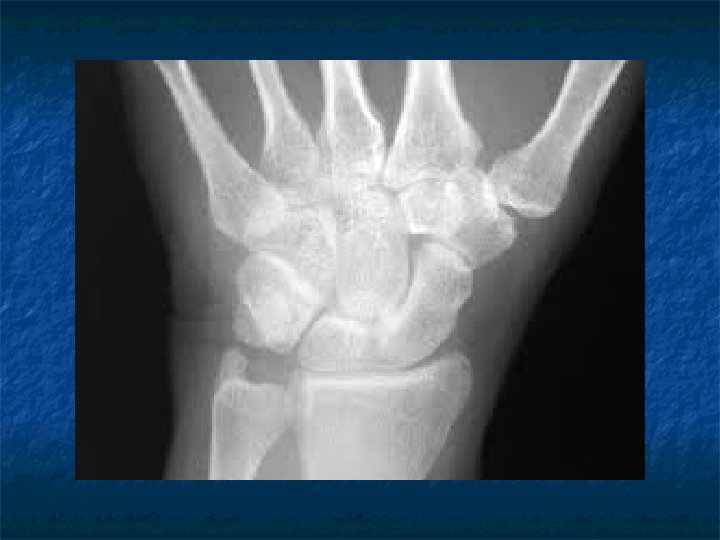

n Dişler yardımıyla ırk, cinsiyet ve yaş tayini

Neleri bilmeliyiz? * * * Ağız ve dişlerin morfolojisi Çevre dokular Morfolojide varyasyonlar Büyüklüklerde bozukluklar Sayısal bozukluklar Sürme bozuklukları Şekil bozuklukları Gelişim bozuklukları Süt dişleri Okluzyon. . .